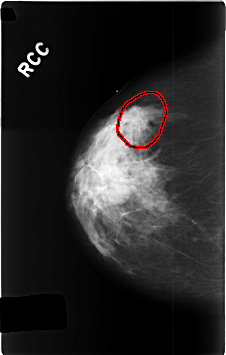

C_0339_1.RIGHT_CC

RIGHT_CC LINES 4608 PIXELS_PER_LINE 2936 BITS_PER_PIXEL 12 RESOLUTION 50 OVERLAY

FILE: C_0339_1.RIGHT_CC.OVERLAY

TOTAL_ABNORMALITIES 1

ABNORMALITY 1

LESION_TYPE MASS SHAPE ROUND MARGINS SPICULATED

ASSESSMENT 5

SUBTLETY 5

PATHOLOGY MALIGNANT

TOTAL_OUTLINES 1

BOUNDARY